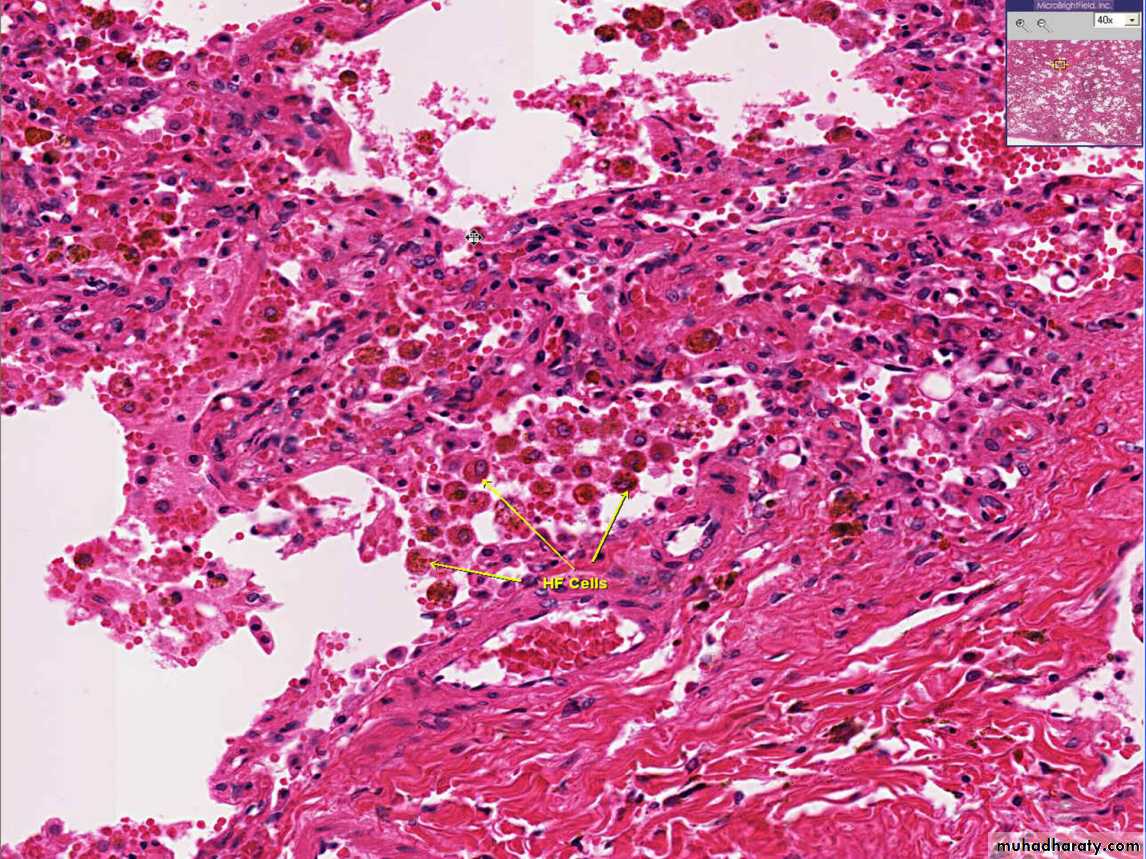

2.Chronic pulmonary congestion

Thickened & fibrotic septaAlveolar spaces contain hemosiderin-laden macrophages (“heart failure cells”) derived from phagocytosed red cells.